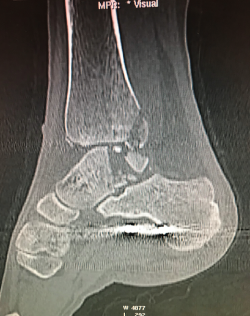

Figura 9. Pseudoartrosis subastragalina.

Se trata de un caso del Dr. Cuervas-Mons, publicado en Techniques in Orthopedics(15), acerca de un paciente varón de 54 años que acude a la consulta con dolor del retropié y deformidad en varo. Tras la valoración, se evidencia pseudoartrosis sintomática (Figura 9), por lo que se decide llevar a cabo tratamiento quirúrgico.

Se presenta un problema: la identificación del plano de pseudoartrosis es fácil de manera preoperatoria con el uso de imágenes; sin embargo, la identificación del plano de pseudoartrosis completo de manera intraoperatoria puede ser difícil, siendo necesario una resección ósea amplia y en ocasiones insuficiente.